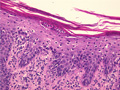

• š(1)Psoriasis (Psoriasis vulgaris)

Macroscopic image: Characteristic well-circumscribed erythematous plaques with silvery scale areseen in the flexual areas of the elbow, knee and buttock. The lesions are not itchy.